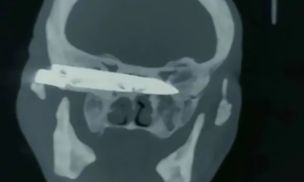

Chiny. Lekarze usunęli nóż z głowy mężczyzny, który żył z nim przez 26 lat